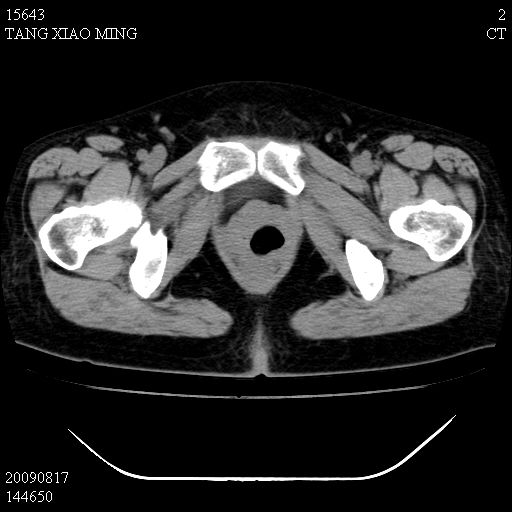

标题: CT21692:盆腔病变

女,33岁,右下腹痛2年余,既往宫外孕病史,如在我院手术,结果下周公布,

可能的诊断。1子宫内膜异位【子宫腺肌症并右卵巢巧克力囊肿】;2 右卵巢囊腺瘤。子宫肌瘤

1)考虑卵巢巧克力囊肿,不排除卵巢囊腺瘤。2)子宫肌瘤可能。

卵巢囊腺瘤,子宫肌瘤,直肠壁厚,不除外占位.